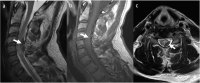

Traumatische spinale Subarachnoidalblutung: ein anschaulicher Fall mit Literaturübersicht // Traumatic spinal subarachnoid hemorrhage with spinal cord compression – a case report and literature review